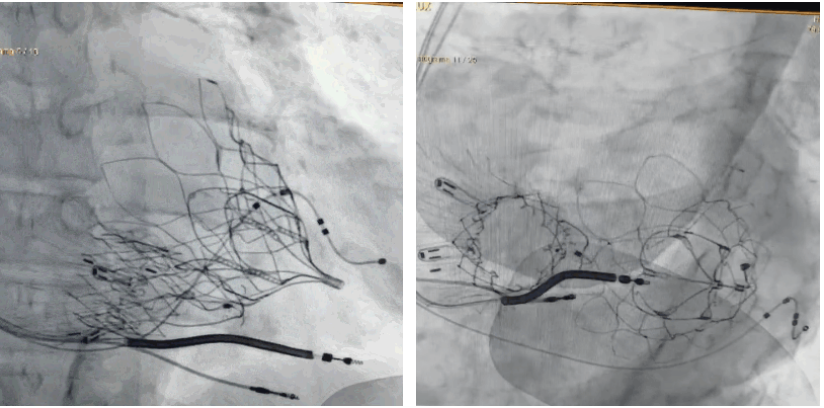

術(shù)后DSA顯示Lux-Valve Plus與Tendyne和ICD無(wú)相互影響

手術(shù)在全麻狀態(tài)下進(jìn)行。術(shù)者采用經(jīng)右側(cè)頸靜脈入路的方式將輸送器送入患者心臟內(nèi),在TEE及DSA引導(dǎo)下調(diào)整輸送器頭端角度,使得輸送器與三尖瓣瓣環(huán)平面垂直。在輸送器進(jìn)入右心室后釋放室間隔錨定裝置,而后釋放瓣葉夾持件(2個(gè)耳片結(jié)構(gòu))成垂直狀態(tài)。在TEE及DSA確定夾持件固定至三尖瓣葉根部且位于右室側(cè)后釋放人工瓣心房側(cè)盤片。隨后調(diào)整瓣膜同軸性以及室間隔錨定件位置(貼合室間隔),前推藏針管并固定,進(jìn)而釋放室間隔錨定裝置,并再次確認(rèn)瓣膜位置、穩(wěn)定性及同軸性,合攏輸送鞘后撤出輸送器,完成LuX-Valve Plus人工三尖瓣瓣膜的植入,僅殘余微量瓣周漏。且經(jīng)手術(shù)中心電生理團(tuán)隊(duì)評(píng)估,病人的起搏器和ICD功能沒有受到影響。

LuX-Valve Plus經(jīng)血管三尖瓣置換系統(tǒng)此次“出海”圓滿完成,術(shù)后Rodrigo Estévez-Loureiro教授對(duì)LuX-Valve Plus經(jīng)血管三尖瓣置換系統(tǒng)的器械性能和治療效果大為稱贊,認(rèn)為L(zhǎng)uX-Valve Plus的手術(shù)體驗(yàn)非常好。術(shù)后即刻超聲顯示三尖瓣反流幾乎完全消失,血流動(dòng)力學(xué)改善顯著,患者恢復(fù)快。在面對(duì)復(fù)雜解剖結(jié)構(gòu)、超聲影像質(zhì)量不佳、有起搏導(dǎo)線干擾時(shí),Lux-Valve Plus也體現(xiàn)了極強(qiáng)的適應(yīng)性。Thomas Modine教授和Anson Cheung教授也肯定了LuX-Valve Plus術(shù)中操作的便捷性,認(rèn)為L(zhǎng)uX-Valve Plus容錯(cuò)率高,對(duì)術(shù)中影像的依賴較小,后期希望可以更多的應(yīng)用LuX-Valve Plus三尖瓣置換系統(tǒng)于臨床實(shí)踐,讓更多的三尖瓣重度反流患者盡早獲益,改善預(yù)后。